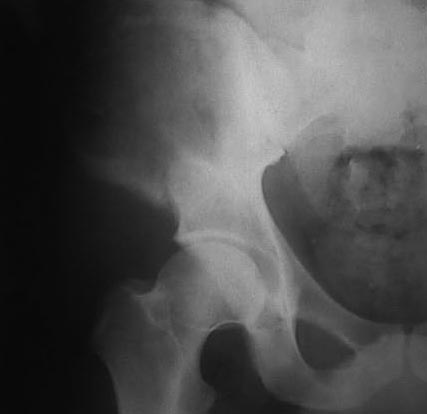

В 2002 году буквально "промелькнул" и исчез пациент с подобным остеолизом. Обследован (биопсия ) в отделении костной онкологии, а затем у дерматологов. Причиной остеолиза признан актиномикоз. К сожалению в то время не удалось выполнить КТ, а рентгенограммы не качественные - в приложении.